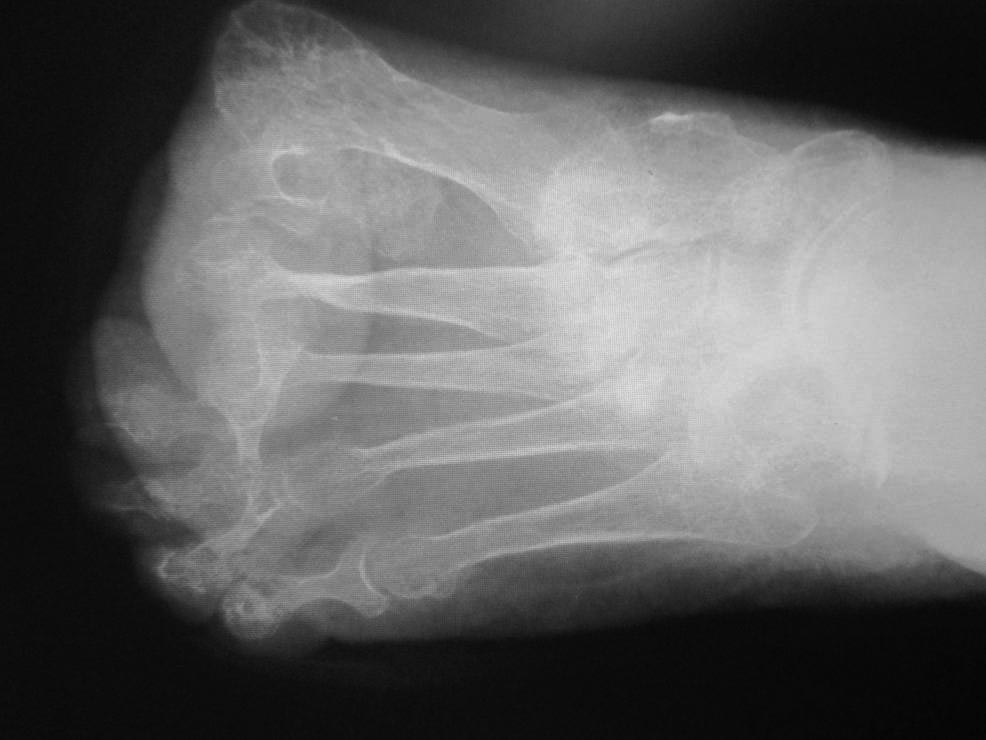

[Ortho] Hallux abductovalgus

Обратилась больная 75 лет с нallux abductovalgus. начало деформации

отмечает с 16 лет.

лечение не проводилось. причина обращения - появление болезненных,

длительно незаживающих пролежней на подошвенной поверхности головок 1-х

плюсневых костей.

Уважаемые коллеги,подскажите пожалуйста план реконструктивной операции.